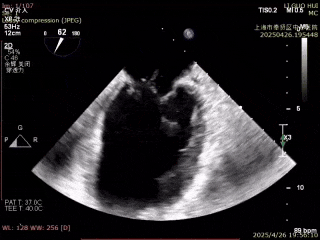

术前二尖瓣重度返流

术后二尖瓣轻度反流